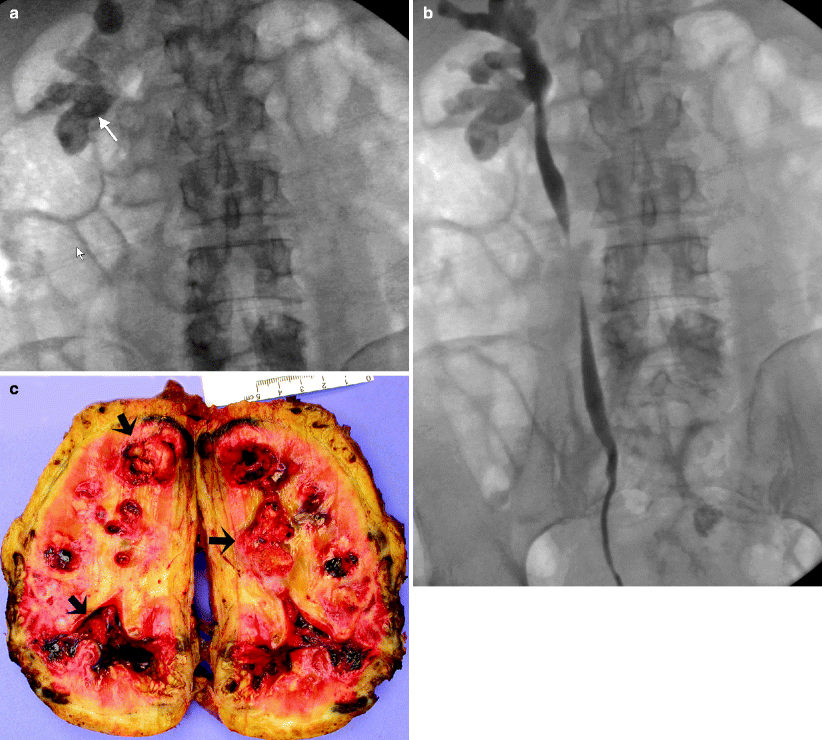

Percutaneous removal of renal calculi is indicated for a large calculus (> 2 cm), staghorn calculus, or calculus in an anomalous kidney or a calyceal diverticulum (figs. Urinary calculi are solid particles in the urinary system. They may cause pain, nausea, vomiting, hematuria, and, possibly, chills and. Scout intravenous urogram obtained after lithotripsy shows absence of the. Approximately 90% of urinary tract calculi are. Scout intravenous urogram demonstrates radiopaque left renal calculi in the mid kidney and lower pole.

No Radiopaque Renal Calculi . Approximately 90% of urinary tract calculi are. They may cause pain, nausea, vomiting, hematuria, and, possibly, chills and. Urinary calculi are solid particles in the urinary system. Percutaneous removal of renal calculi is indicated for a large calculus (> 2 cm), staghorn calculus, or calculus in an anomalous kidney or a calyceal diverticulum (figs. Scout intravenous urogram demonstrates radiopaque left renal calculi in the mid kidney and lower pole. Scout intravenous urogram obtained after lithotripsy shows absence of the.